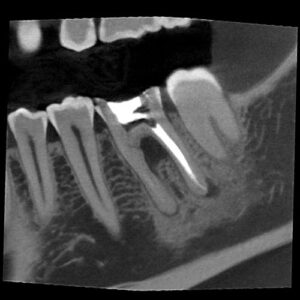

UHD Mode for Endodontics

PreXion Excelsior MID has a resolution with Isotropic Voxel of 75μm to 250μm.

Metal Artifact Reduction (MAR)

The PreXion Excelsior MID line features three processing levels that can be chosen to correct gutta-percha deformities, implants and/or full arch prosthesis and metal restorations, in addition to automatic metal reduction. This tool also allows image reprocessing, for a better diagnosis, preventing the need to generate new exposure to the patient.